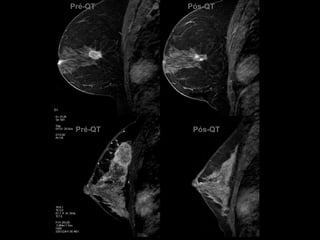

Pré-QTPré-QTPós-QTPós-QT

•Avaliar a resposta tumoral durante o tratamento para determinar ou não a continuidade da terapia.

•Avaliar a extensão da doença residual após o tratamento para estabelecer a extensão da ressecção cirúrgica. Avaliação da resposta á quimioterapia neoadjuvante

•RM é o melhor do que os métodos convencionais e o exame físico na avaliação da resposta terapêutica e para estimar a doença residual após o tratamento.

•Não é necessária em todos os casos.

•Quando for utilizar é necessária uma RM pré-tratamento para correlação. Avaliação da resposta á quimioterapia neoadjuvanteTardivon et al. Eur Radiol 2006; 16: 2549–2558

•Avaliação da resposta durante o tratamento:

•Carcinoma lobular invasivo.

•Mamas densas.

•Doenças multicêntricas / multifocais.

•Lesões calcificadas.

•Puéperas.

•Avaliação da doença residual pós -tratamento:

•Candidatas á cirurgia conservadora.

•Extenso envolvimento da parede torácica.

Avaliação da resposta á quimioterapia neoadjuvante